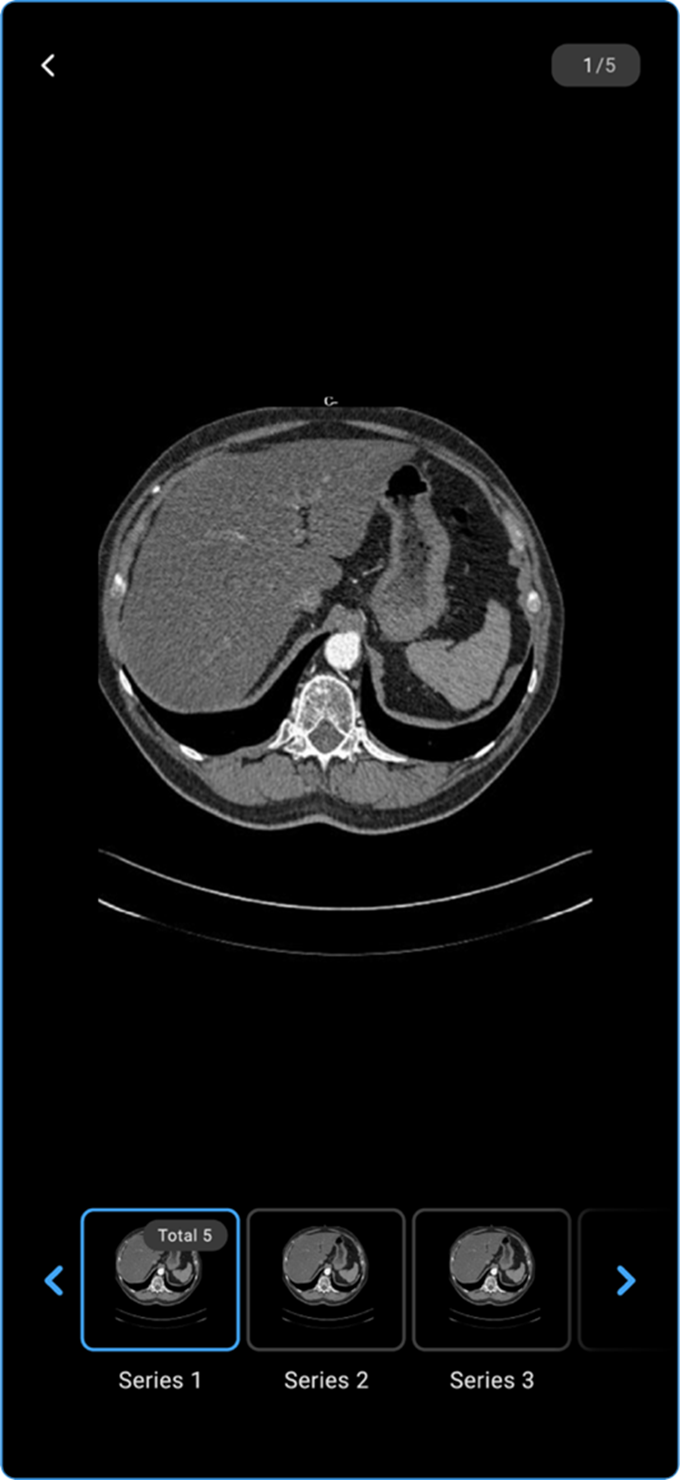

Mobile

1. Access Completed Appointments

Log in and navigate to Completed Appointments, then select the study you wish to view.

2. View Results

Tap View Results to see available options:

1. View Images — Opens attached study images in the Blume Image Viewer.

a. Swipe up to scroll through series, right to move between frames.

b. Pinch to zoom in or zoom out.

c. Tap the back arrow (top-left) to exit the viewer.

Viewing Images in Completed Appointments

• Go to Completed Appointments and select the desired study.

• Tap View Results to open the Study Information Page.

vai

• Locate and tap View Images to access the available images.

• Use finger touch to PAN the images.

• Pinch in/out to zoom in or out.

• Scroll sideways to navigate through other images in the series.